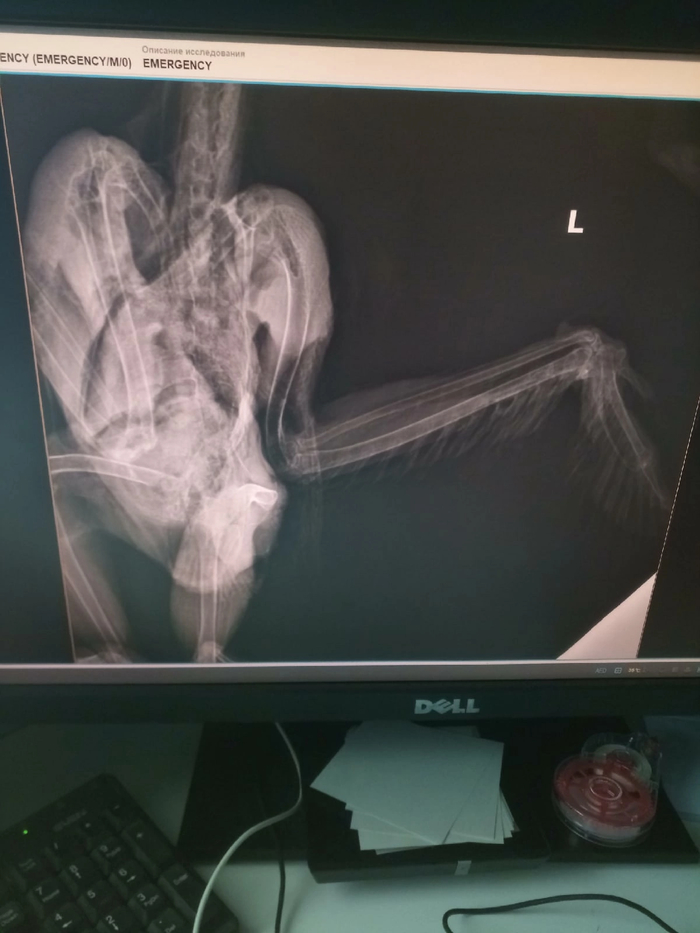

Сделали рентген по результатам которого предположительно пневмония, восполнение воздухоносных мешков и ЖКТ.

Рентген надо переделать, во вторник поедем к другому рентгенологу. Пока вроде как сказали, что увеличена почка. Крыло себя ожидаемо чувствует не очень хорошо,но надеемся сохранить .